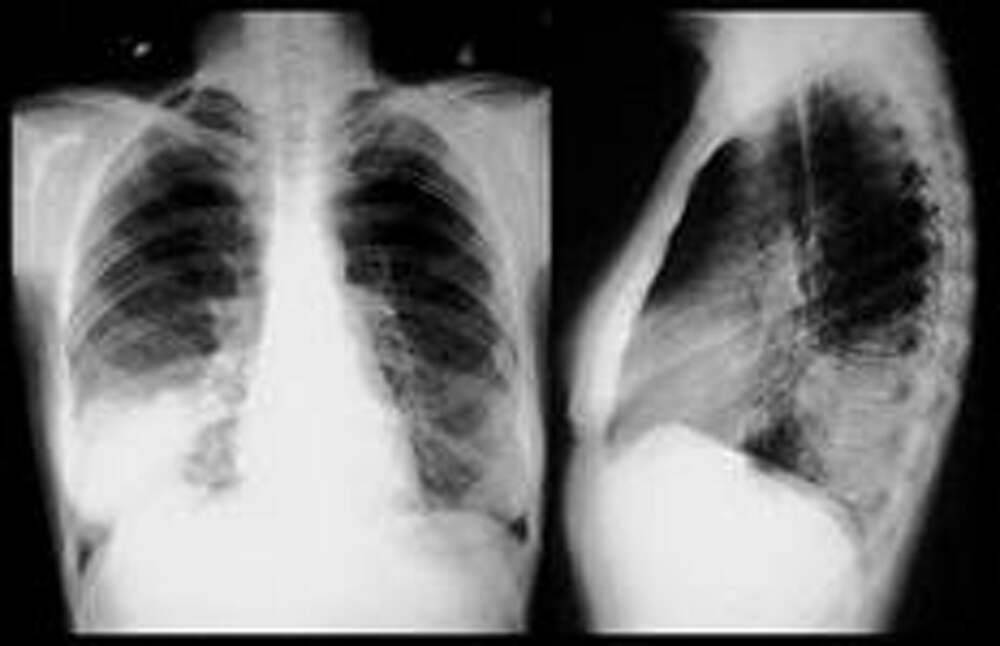

Пневмония у ребенка

Если воспалительный процесс, поражающий органы дыхания, распространяется на мельчайшие легочные пузырьки-альвеолы, составляющие основу легкого, то возникает заболевание, называемое пневмонией. Особенно часто болеют пневмонией дети первого года жизни. Несмотря на имеющиеся высокоэффективные методы